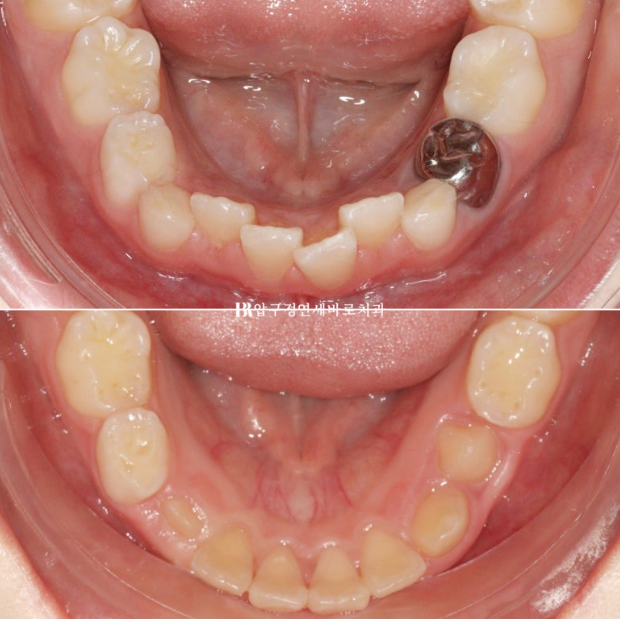

2022.11~2024.06

첫장치는 43개였고 두번째는 17개였으니 총 60개의 장치 5일씩 착용했던 아이니까 300일의 총 치료기간입니다.

2024.6.4

미리 충분하게 만들어놓은 공간으로 송곳니 등 후속 영구치들이 맹출하고 있습니다.

영구치가 적절한 수준까지 올라오면 고정식 유지장치까지 해줄 계획입니다.

이 친구는 아마 영구치열에 2차 교정이 따로 필요 없을 것 같습니다.